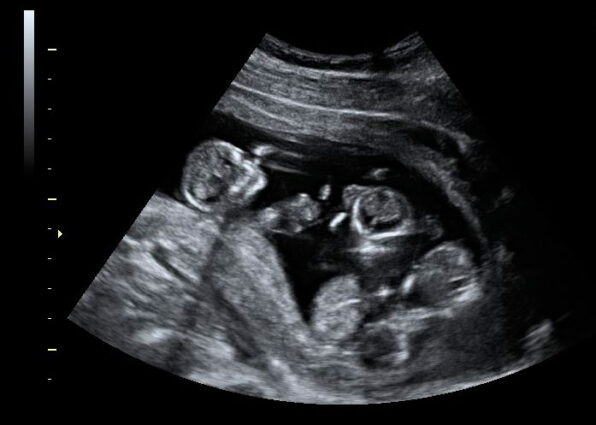

Andrea Cardoso (19) y Jorge Luis Murattore (22) recibieron la impactante noticia el 25 de enero, cuando una ecografía confirmó que su familia crecería por tres. Actualmente, transitan la décima semana de gestación con gran expectativa y emoción.

La sorpresa fue aún mayor cuando, tras la confirmación del embarazo, la ecografía reveló tres latidos. “Ni siquiera el mismo doctor podía creer lo que estábamos viendo”, agregó.